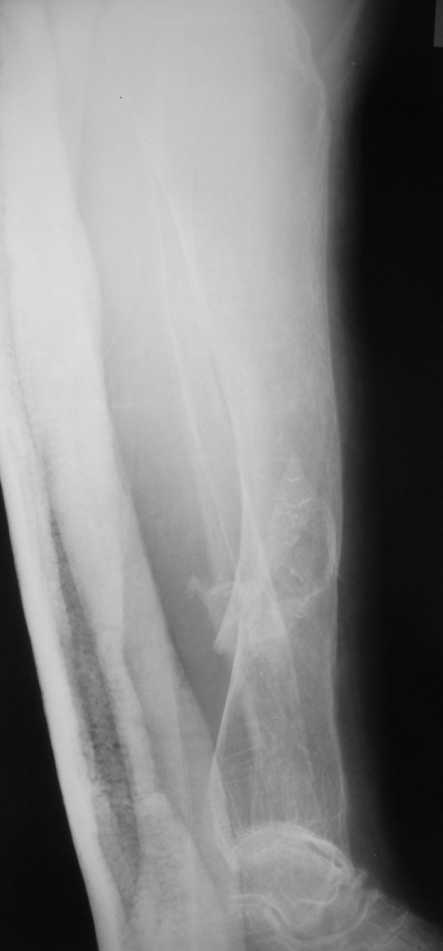

Но даже при малоинвазивной методике лечения применимой для даной больной существуют следующие проблемы: выраженный остеопороз, тонкий кортикал, очень широкий канал.

Контрольные рентгенограммы прилагаю.

Проблема в том, что в сагитальной плоскости угол голеней =30 градусам. Ширина канала 30.

ДС> Проблема в том, что в сагитальной плоскости угол голеней =30 градусам. Ширина канала 30.

Если при введении стержня будет видно, что из-за искривления дело идет к перфорации стенки, надо будет сделать чрескожную остеотомию на уровне кончика стержня.

Во-1-х, интрамедулярный остеосинтез относится к методам, дающим относительную, не абсолютную стабильность. Во-2-х, стабильность неплохо обеспечивается запирающими винтами. В-3-х, несоответствие кривизны стержня и канала приводит к повышению стабильности, в-4-х, канал можно искусственно сузить введением отклоняющих (трансмедуллярных, Poller) винтов.